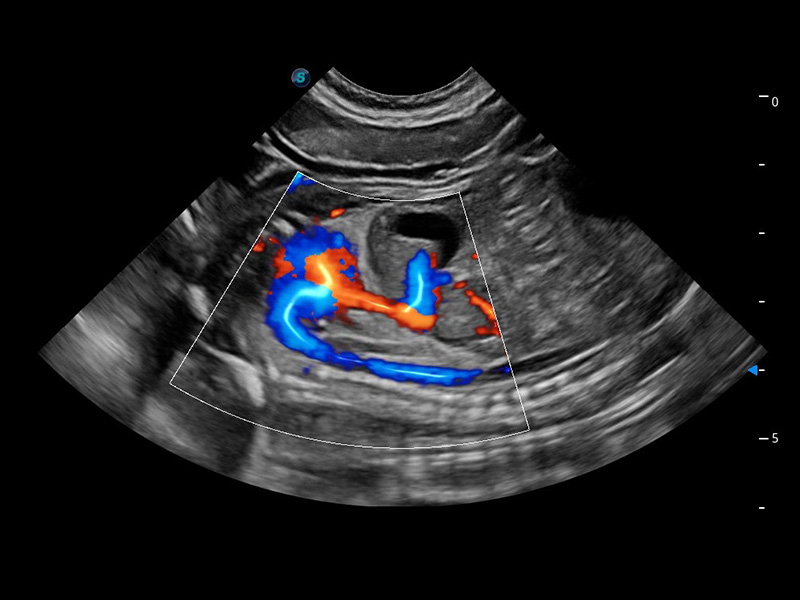

ProPet 60 作为一款高端台式动物超声设备,为动物医生的日常诊断提供了一系列贴合动物临床需求、解决临床实际问题的高级成像功能。凭借全系列高清探头,满足医生对腹部、心脏、生殖、浅表、肌骨等成像的所有需求,切实帮助您提升检查效率,提高诊断信心。

动物是人类最亲密的朋友和最值得信赖的伙伴。米兰官方网站也一直致力于探索动物专用的超声影像解决方案。 全新推出的ProPet系列,是米兰官方网站在动物超声影像智能化、专业化、精准化的一次跨越式革新。动物不能用言语来表述自己的不适,通过超声影像,ProPet系列搭建了动物医生与不同物种沟通的“桥梁”,为动物医生注入了“治愈之力”。